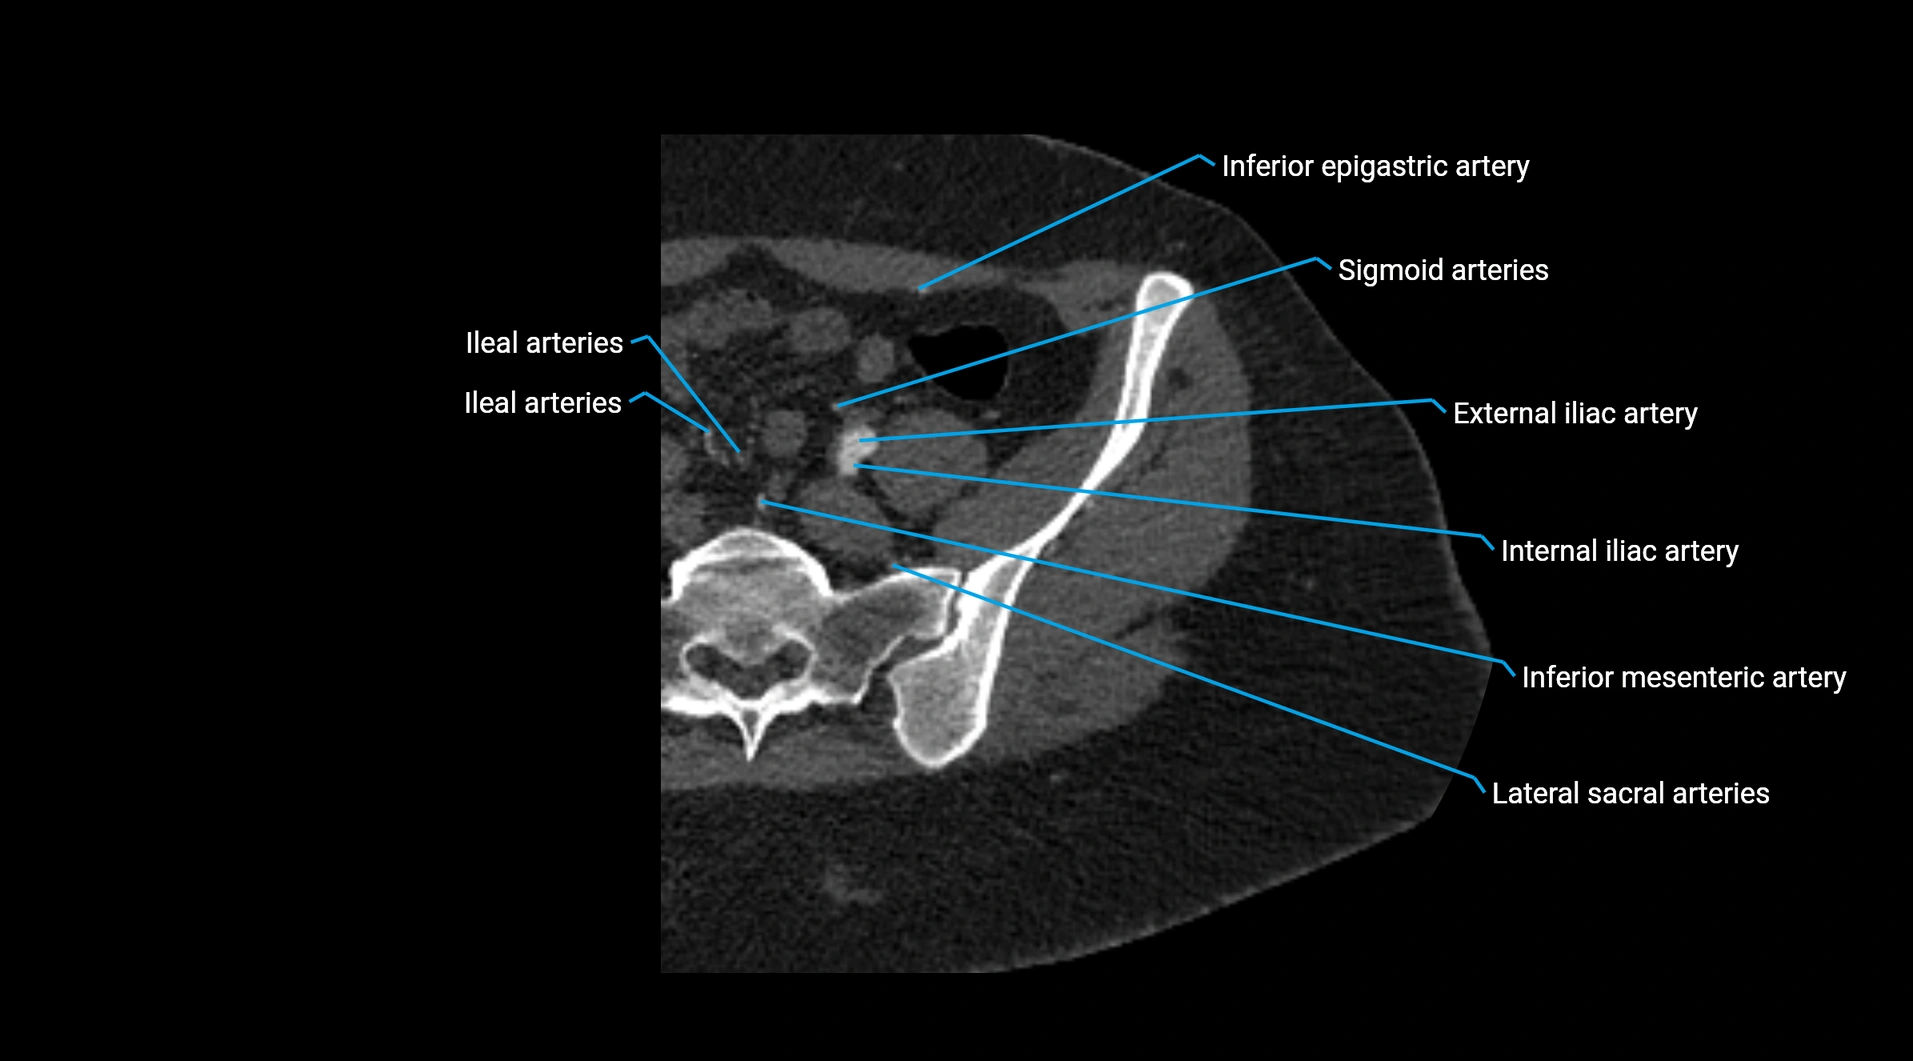

CT images

image